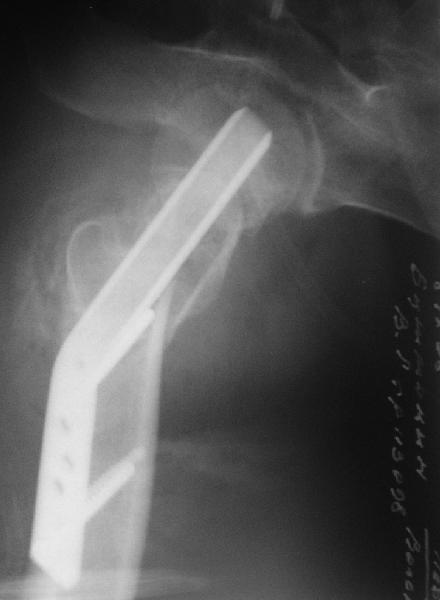

Приветствую всех. Спасибо за активное участие в обсуждении. Выбрали вариант с остеотомией.

Снимки в приложении.

Надеемся на днях поднять на костыли.